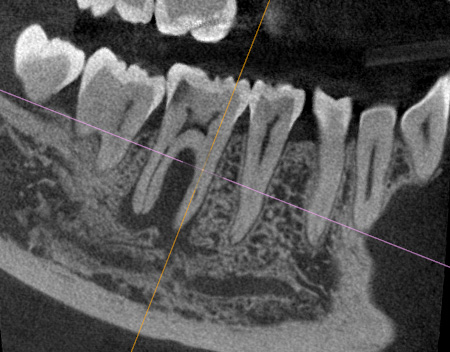

Endodontic treatment as a treatment for sinusitis of odontogenic origin

Read article